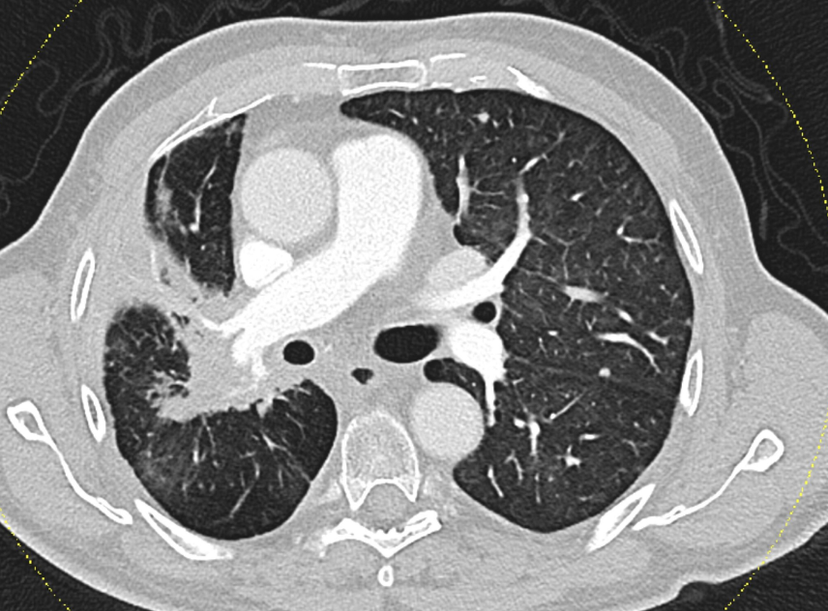

Precise planning ensures safety

The study highlights the potential for more personalized treatment strategies in patients with unresectable NSCLC. “For selected patients with stable lung function, intensified radiotherapy could significantly improve overall survival,” adds Dr Schragel. “And I’m particularly pleased that KL Krems is taking a leading role in this area – producing research with direct relevance for clinical practice.” At the same time, the findings underline the importance of regularly re-evaluating established treatment thresholds in the light of evolving treatment approaches such as immunotherapy.